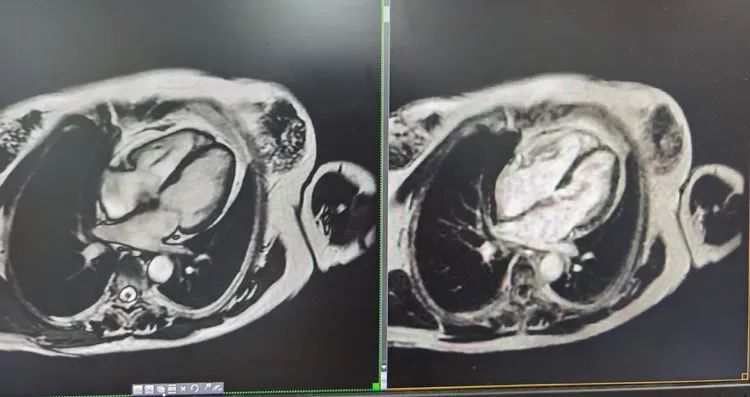

▲心脏核磁平扫及灌注图

心脏核磁共振是指运用磁共振无创成像技术,对心脏疾病进行诊断的先进检查方法,具有良好的软组织对比分辨率。完成一次心脏全套核磁(平扫+增强),需要30分钟至40分钟左右。

★一站式检查,可以回答关于室壁运动、心脏功能、定量分析、心肌活性等相关心脏问题。

★心脏磁共振是评价心功能的金标准,更有利于瓣膜及心脏微小病变的显示,此外具有更大视野、多方位成像。可以避免一些由肋骨、肺组织造成的干扰,灌注和心肌活性检查更是磁共振无可比拟的优势。★心脏核磁能更早、更有效的发现病变,全面显示心腔、心肌、心包及心内其他细小结构。